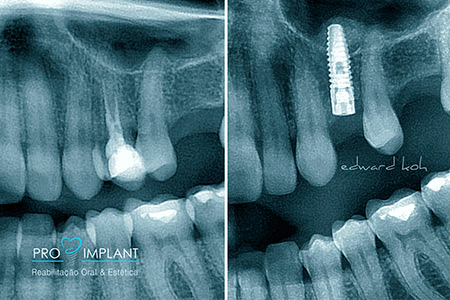

A perda de dentes pode levar a problemas estéticos, de oclusão (mordida) e perda óssea. Portanto é fundamental uma rápida reposição do elemento perdido. Os Implantes Dentários são parafusos de titânio que substituem a raiz dos dentes perdidos. O implante dental serve de apoio para a prótese (coroa) que deve ser semelhante aos dentes: naturais em estética e função. Os Implantes Dentários podem ser indicados para repor a perda de todos os dentes, de alguns ou de apenas um dente.

O Implante Dentário inibe a atrofia do osso após a perda de um dente; é fixo e não há necessidade de comprometer os dentes naturais adjacentes.